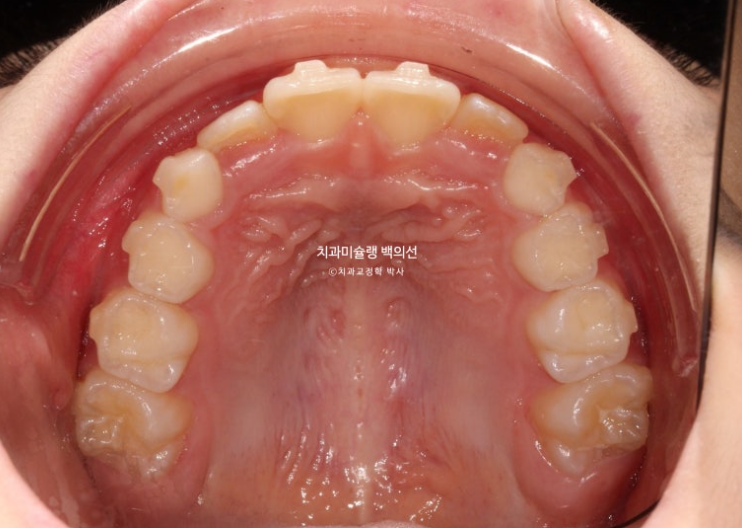

2년 전 교정치료를 위해 내원한 만 8세 어린이입니다.

이제 겨우 유치 앞니가 빠지고 영구치 앞니가 나오는 시기인데

앞니부터 심한 덧니로 내려오니 부모님이 놀라서 오셨습니다.

이 날 자리가 좁으면 치아가 회전된 상태로 나오거나 입천장으로 나오거나 이 친구처럼 덧니로 내려오게 됩니다.